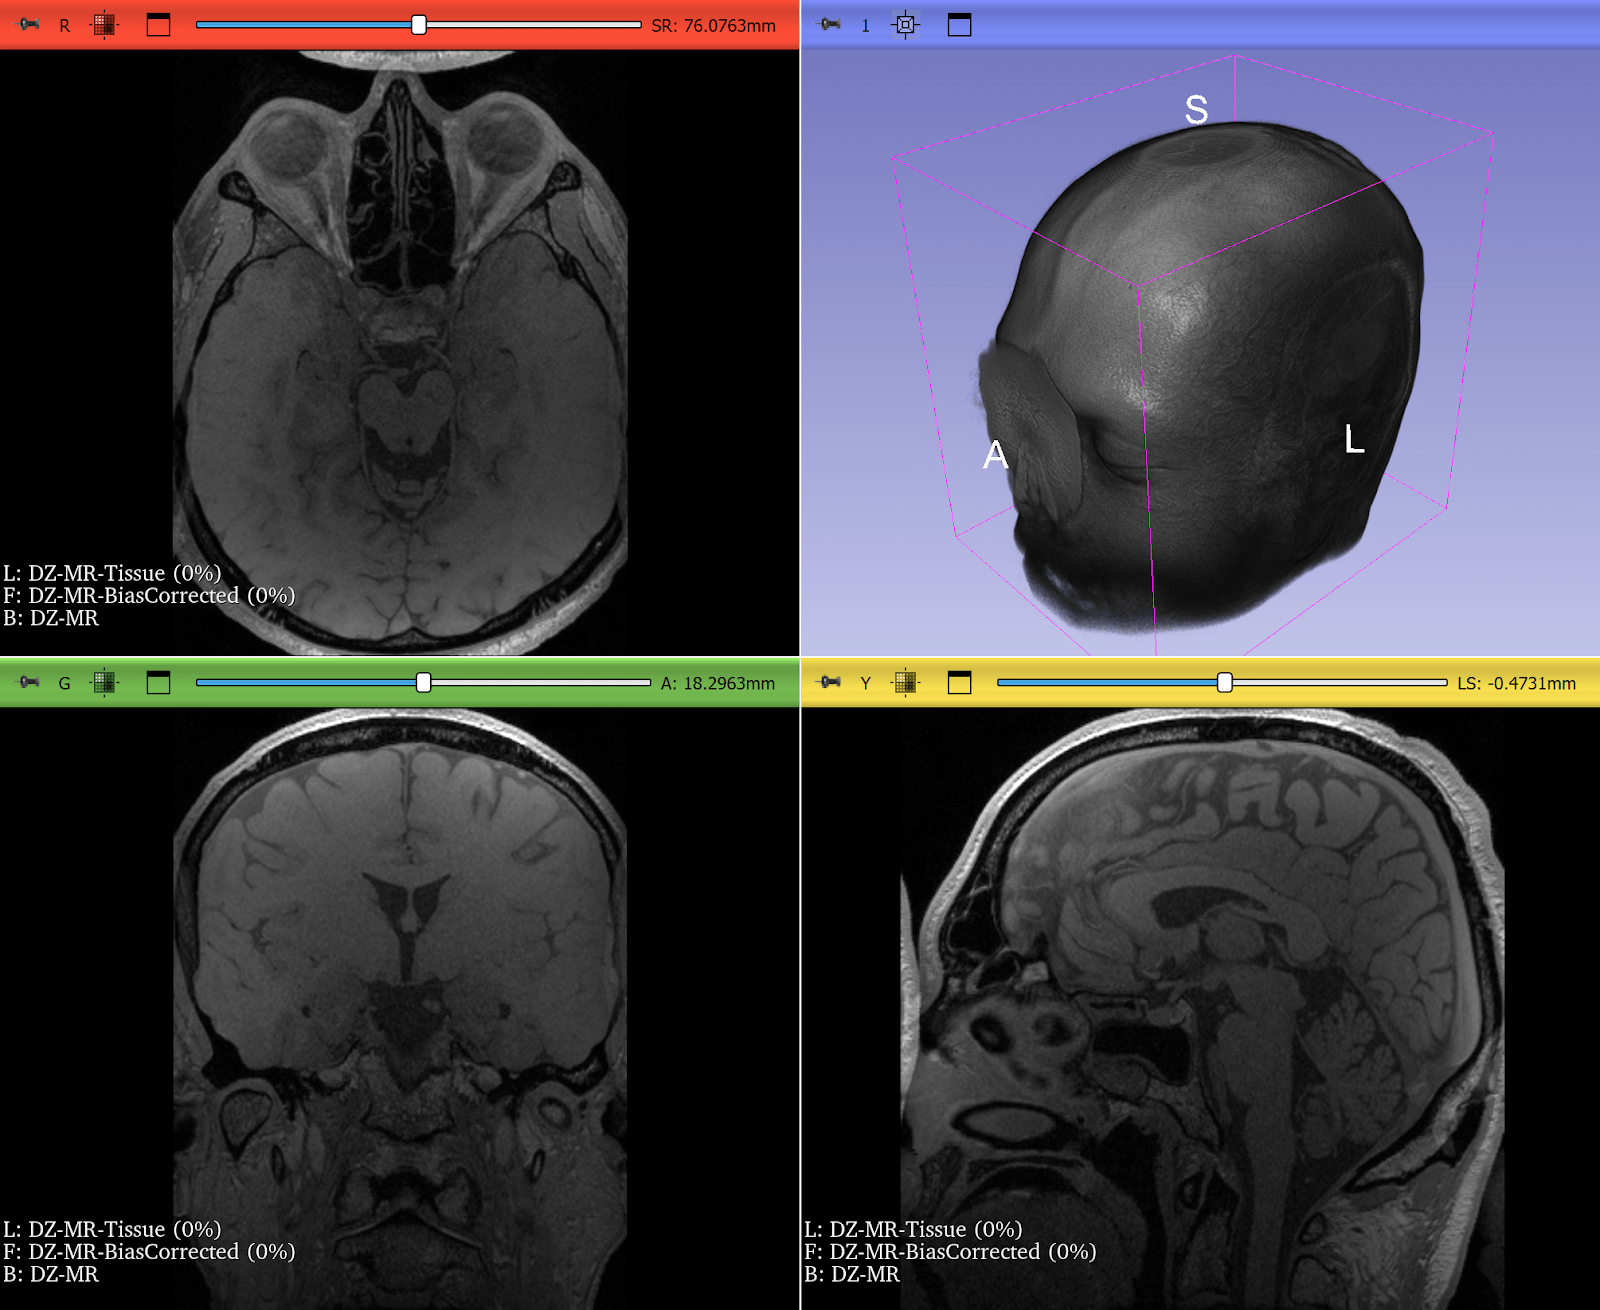

Bias Field Correction in Brain MRI

Magnetic resonance imaging (MRI) is prone to intensity inhomogeneities, also called bias fields. These low-frequency variations in intensity are not biological but caused by scanner physics. Deep learning models trained on uncorrected data risk learning scanner artifacts instead of tissue features.

ITK’s N4BiasFieldCorrectionImageFilter has become the gold standard for correcting this problem. With just a few lines of code, researchers can normalize the intensity profile of brain MRIs, making data consistent across scanners and institutions.

This correction is now a standard preprocessing step in brain tumor segmentation challenges and pipelines, ensuring that CNNs see consistent, biologically meaningful data. If a neural network is expected to encounter MRIs with intensity inhomogeneities, they can be intentionally introduced during training by using appropriate augmentation. Examples include RandBiasFieldd from MONAI and RandomBiasField from TorchIO. It can be even accomplished just by doing BiasFieldCorrection in reverse, starting from a corrected image and applying a randomly-generated bias field.

Figure 2: T2* Weighted MRI of the brain, before and after correction of intensity inhomogeneity. Bias field correction was done using 3D Slicer, another application prominently using ITK. Use left-right slider to compare before vs. after.